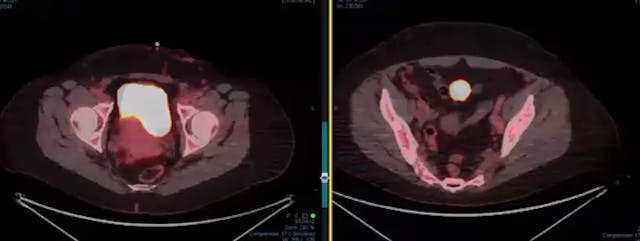

07/18/2024 - Dr. Christine Fisher - Radiation Oncology - GYN

Chartrounds US - GYN